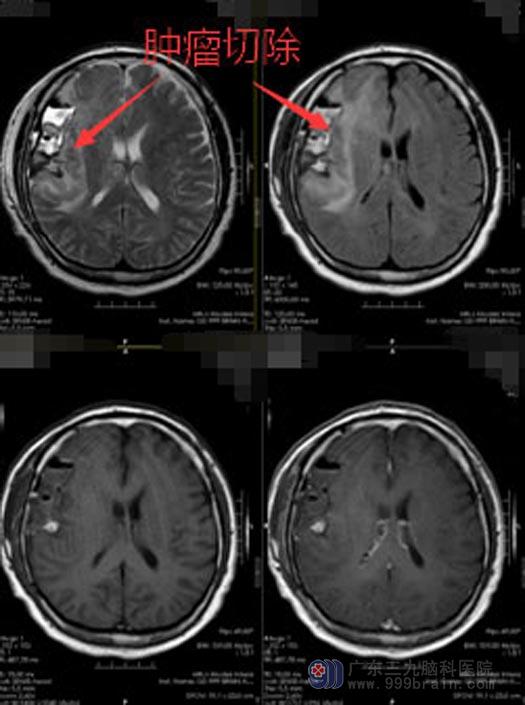

为了能够最大限度地切除病灶,同时又能最大程度保留患者脑功能,神经外五科鲁明治疗团队经过慎重讨论,在取得潘大叔及家人的同意后,决定在术中唤醒麻醉下行颅内占位切除术。术程顺利,术中患者语言、肢体运动配合良好。病变呈弥漫性,做了最大可能的切除后,患者的神经功能保护好,术后语言和运动功能同术前无加重。病理证实弥漫性星形细胞瘤,目前潘大叔恢复良好,准备下一步的放射治疗。